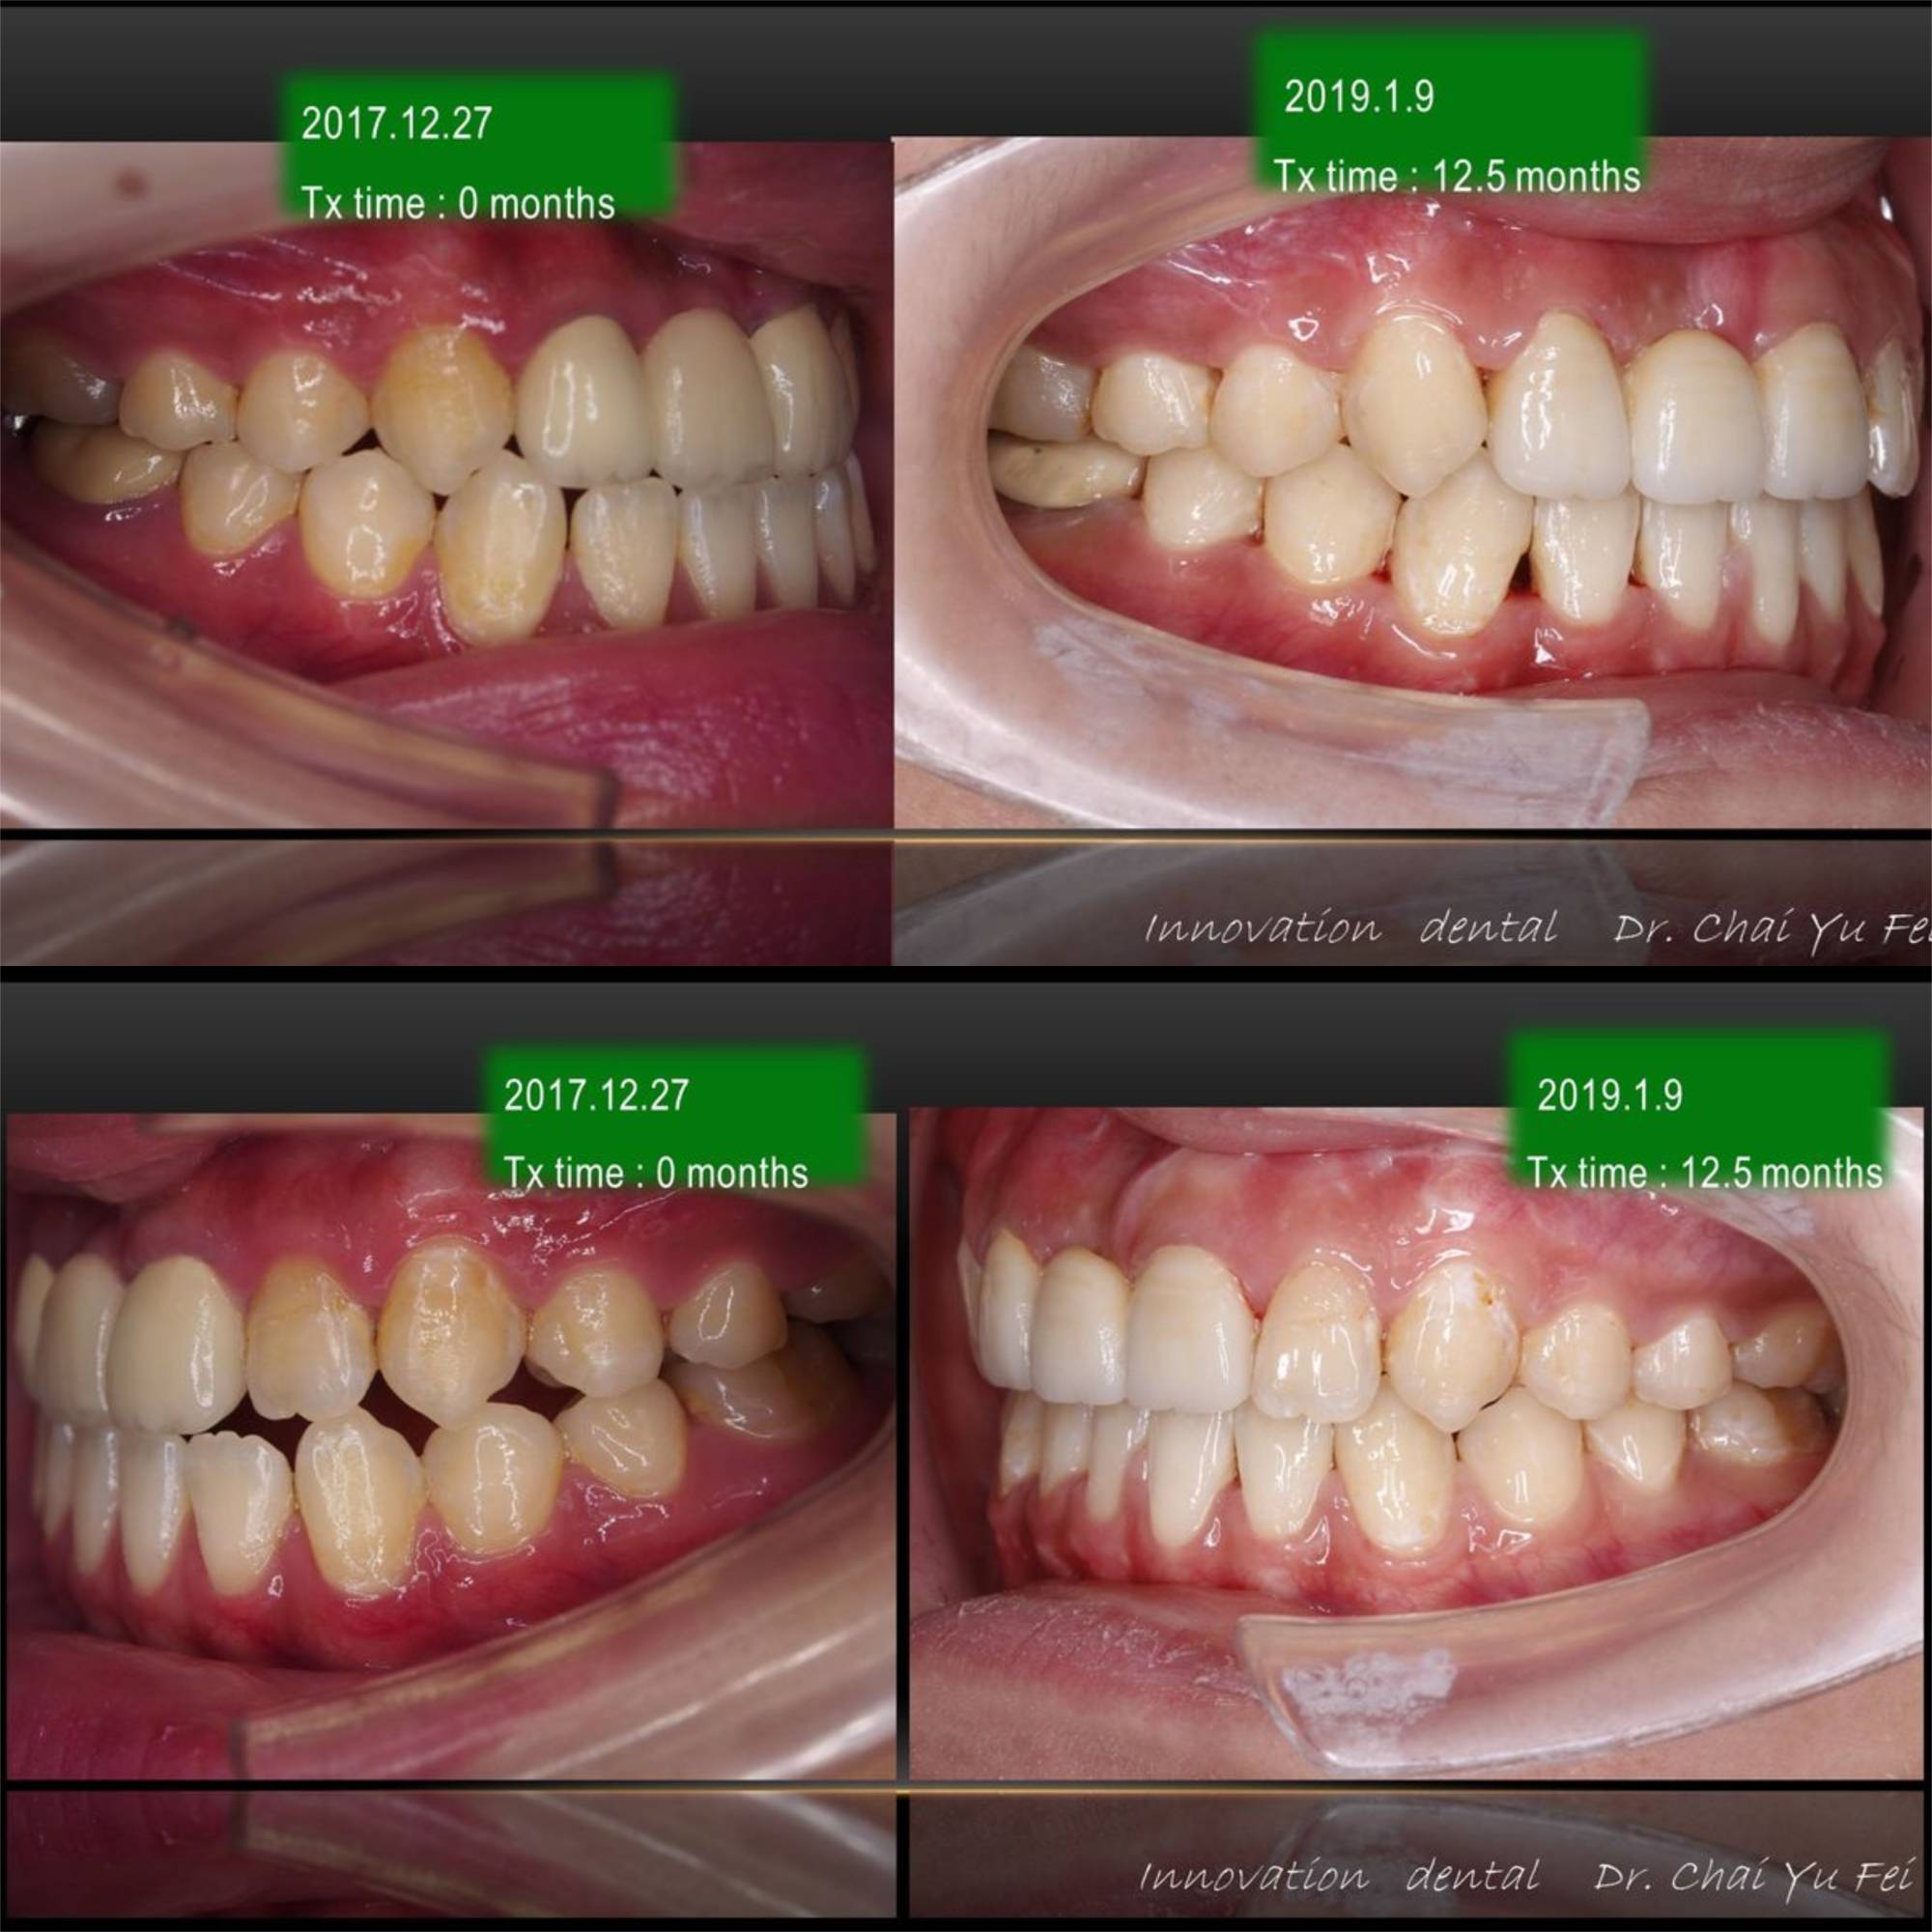

[ 治療時間 ] : 12.5 個月

從患者的側面來看,上下唇都是不能夠自然地閉上嘴巴,經過幾個月的準備,已經達到手術前標準,接著術後調整到理想的外觀.

讓我們來看看她術前術後的成果吧~

術後笑起來的感覺非常和諧

原本厚道嘴唇無法自然關閉的情形也改善了許多。

下顎咬合平面打平,藉由手術後退達到理想咬合。

經由我的矯正治療與陳人瑄醫師的正顎手術,林同學可以開心地微笑了~